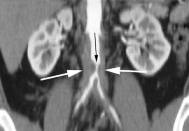

Mitralna stenozaKod umereno teske mitralne stenoze( mitralno usce 1-1,5 cm2 ) minutni volumen se pri naporu nedovoljno povecava i moze dovesti do pasivne plucne hipertenzije i plucnog edema. Kod teske mitralne stenoze (mitralno usce manje od 1 cm2) minutni volumen u miru je nedovoljan, aklinickom slikom dominira slabost i umor.Kad srednji pritisak LP poraste do 20mmHg dolazi do funkcionalne plucne hipertenzije, plucni edem se povlaci,ali dolazi do daljeg porasta pritiska u PA i opterecenja DK.Razvojem anatomskih promena u krvnim sudovima pluca, DK hipertrofira, dilatira, razvija se trikuspidalna, nekada i pulmonalna regurgitacija.Razvijaju se santovi izmedju plucnih i bronhijalnih vena smanjujuci plucnu komplijansu,a tok krvi se usmerava od baze ka vrhovima pluca.